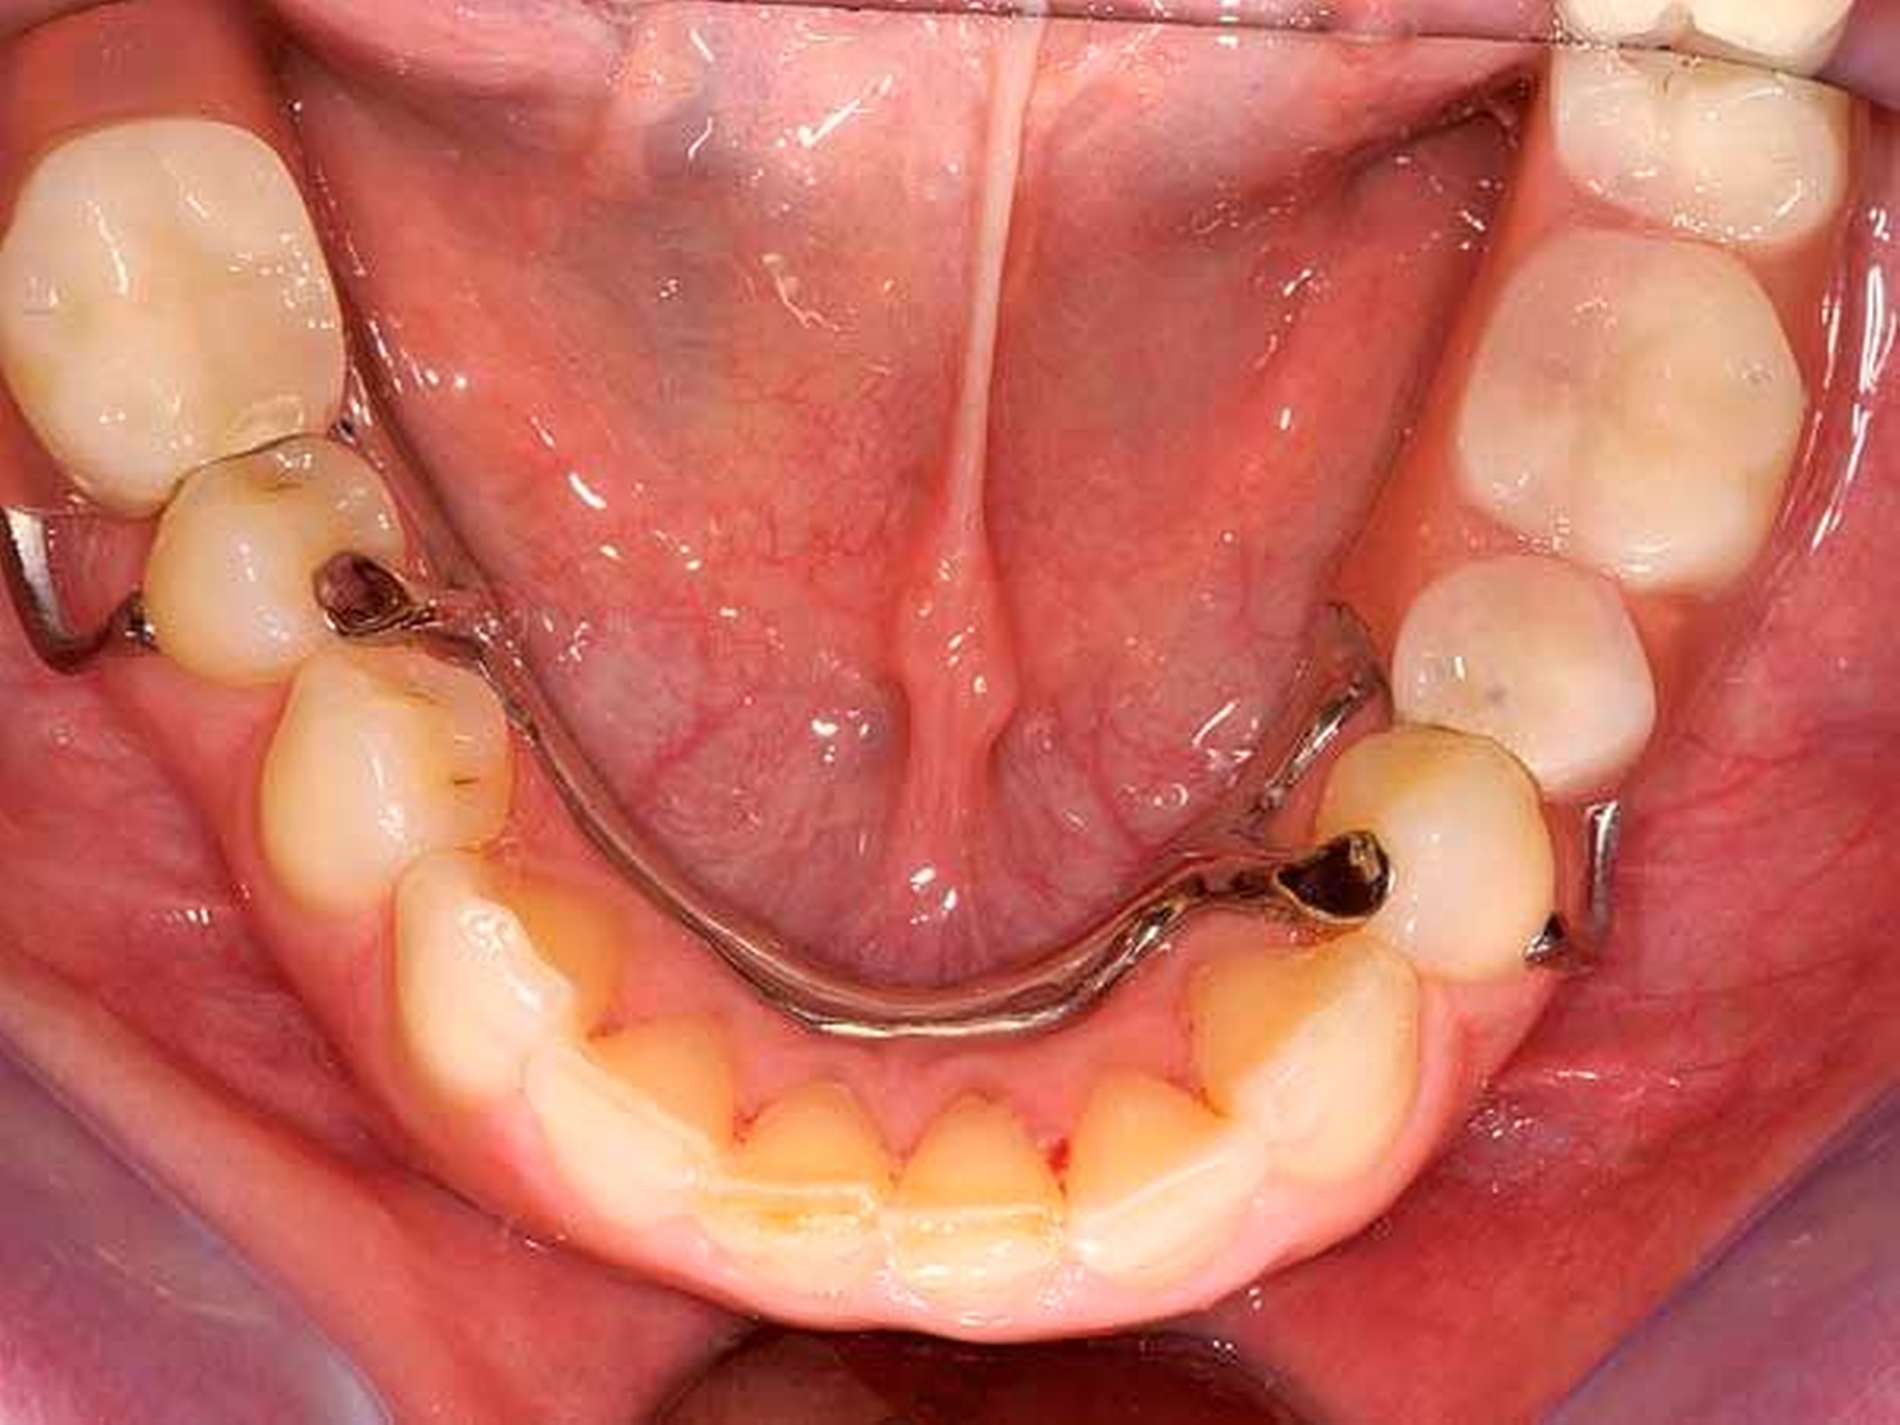

Das Orthopantomogramm (Abbildung 7) zeigt die Gebisssituation eines 89-jährigen Patienten mit kardiovaskulärer Anamnese (Herzinfarkt, Stent-Implantate) und deutlich reduziertem, fast hinfälligem Allgemeinzustand. Der Patient erhält 14(!) verschiedene Medikationen. Der überweisenden Kollegin erschien die Behandlung in der Praxis zu riskant. Nach Abschluss der Extraktionstherapie stellte sich der Patient zur prothetischen Beratung und Weiterversorgung an unserer Poliklinik vor. Im Oberkiefer wurde ein totaler Zahnersatz geplant. Im Unterkiefer verblieb ein karies- und füllungsfreies Restgebiss von 33 nach 42 (Abbildung 8). Aus gesundheitlichen Gründen schied eine Präparation der karies- und füllungsfreien Zähne für die Aufnahme von Doppelkronen oder metallkeramischen Kronen mit oralen Fräsungen aus.

Front- und Eckzähne sind aufgrund ihrer Anatomie grundsätzlich schlecht für die Aufnahme von Gussklammern geeignet. Die Lösung in diesem zweiten Fall bestand in der Anwendung zweier geteilter Klammern (Roach-Klammer), ausgeführt als Druckanker (Abbildungen 9 und 10). Lingual wurden die Zähne 33 und 42 mit den oralen Klammerarmen großflächig von disto- nach mesioapproximal gefasst. Gegebenenfalls müssen, nach Augenmaß senkrecht zur Einschubrichtung, die Tuberculi und der distoapproximale Kontaktpunkt im Schmelz mit einem Diamantfinierer leicht abgeflacht werden. Die Präparation für die orale Klammerauflage in Höhe der Tuberculi muss konsequent als Stufe von 1 mm Tiefe parallel zur Okklusionsebene eingeschliffen werden. Die Auflage selbst ist in den oralen Klammerarm integriert. Die vestibulären Retentionsarme liegen dem Zahn nicht passiv an, sondern stehen unter Vorspannung und drücken den Ankerzahn bei eingegliedertem Zahnersatz aktiv gegen das starre Widerlager der oralen Umfassung. Dies sichert in Verbindung mit der weiten, fast geschiebeartigen oralen Fassung und der integrierten Klammerauflage eine akzeptable Kippmeiderfunktion.

Die großflächigen Umfassungen der oralen Ankerzahnflächen erhöhen das Kariesrisiko, dem kann mit adäquater Mundhygiene und Fluoridierung begegnet werden. Zur Optimierung der parodontalen Hygienefähigkeit wurden die Regeln der „Grenzraumgestaltung nach Marxkors“ (brückenzwischengliedartige Gestaltung des ersten Prothesenzahnes mit metallischer Basis, Durchspülbarkeit, Insertion des sublingualen Bügels in den Sattel eine Prämolarenbreite hinter dem endständigen Zahn [Marxkors, 2007]) konsequent umgesetzt (Abbildungen 11 und 12).